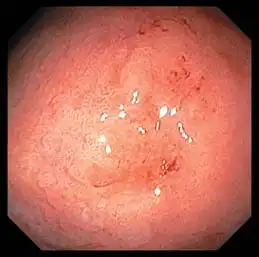

Advanced Image Clarity

Two light guides provide amplifi ed brightness to support accurate depiction of mucosal structures.

White Light NBI